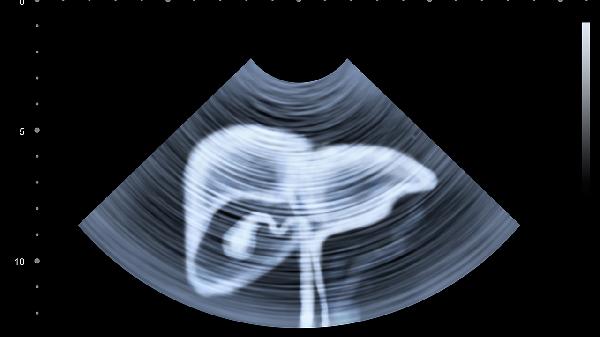

胆囊切除后胆总管代偿性扩张可能形成继发结石,结石阻塞胆管会引起右上腹持续性胀痛,可能伴随黄疸或发热。确诊需通过磁共振胰胆管造影检查,治疗可采用内镜下乳头括约肌切开取石术,必要时联合熊去氧胆酸等利胆药物。

腹腔手术史可能造成局部肠管粘连,表现为进食后腹胀加重伴间歇性隐痛。超声或CT可见肠袢固定,初期建议清淡饮食配合腹部按摩,严重粘连需腹腔镜松解手术。